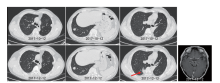

按照MTD讨论意见, 虽然已发现颅内转移结节, 但肿瘤生长非常缓慢, 转移病灶不足1 cm, 遂予继续观察。2017-10-12复查CT及头颅MR提示肺内结节无变化, 左颞叶病灶约7 mm, 9个月观察随访没有变化, 继续随访不加干预。2017-12-12行CT提示新发右下肺结节, 大小约2.0 cm, 肺部其余结节无变化, 头颅MR提示左颞叶结节0.8 cm(见图2)。